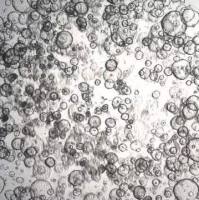

类器官分化流程。人结肠类器官可以通过定形内胚层、后肠内胚层和结肠类器官扩增阶段,使用三步分化方案从人 iPS 细胞生成。 SCM302:定形内胚层诱导培养基,SCM303:后肠诱导培养基,SCM304:3dGRO™ 人结肠类器官扩增培养基 类器官培养方案 步骤1:人 iPS 细胞分化为定形内胚层(第 0-4 天) 注意:起始材料为高品质未分化的人 ES/iPS 细胞(SCC271)(细胞融合度约为 70-80%,且含有 准备单细胞传代培养基。将 ROCK 抑制剂 (ROCKi) Y

在自然界,许多动物拥有着令人惊叹的再生能力,比如「超级选手」海星、蝾螈、斑马鱼(心脏可再生)、扁虫(头部可再生)……科学家们一直希望将这些神奇应用于生命科学,解决器官移植、药物开发等问题。干细胞是组织再生的「源泉」,在此基础之上诞生的「类器官」(organoids)给予了更多的可能。这些在体外培养的微小结构,可以模拟人体器官的复杂结构,还可以重塑体内肿瘤组织的关键特性,有着代替动物试验、实现器官移植的巨大潜力。类器官的获得与治疗潜能01 助力精准医学的「秘密武器」自 2000 年代末,生物